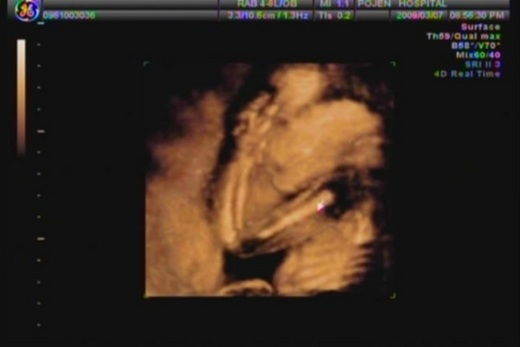

為什麼說我們Nemo第一次差點照不到呢?因為他不知是太害羞還是露錯地方了,都把兩隻小手手放在頭上擋住了他的臉,但卻又很大方的露出他的小鳥鳥給我們看。在前半段時間看不到他的臉,只好先看看他的四肢,雙手雙腳都有看到,連手指腳指一根一根的都看得很清楚,然後就先休息五分鐘,讓我們對Nemo親子喊話,要他乖乖的把手放下來,把拔馬麻好想看到他哦!結果後半段他可終於聽話的把手放下也轉了向讓我們很清楚的看到他的臉呢!雖然看不出像誰,但我第一個感想是"原來你就是我的Nemo啊!"滿滿的感動。

PS:照片就是我們害羞的Nemo,他用小手手把臉臉給遮了起來,雖然沒看到他的臉,但覺得這個動作好可愛哦!所以選擇這張放上來。